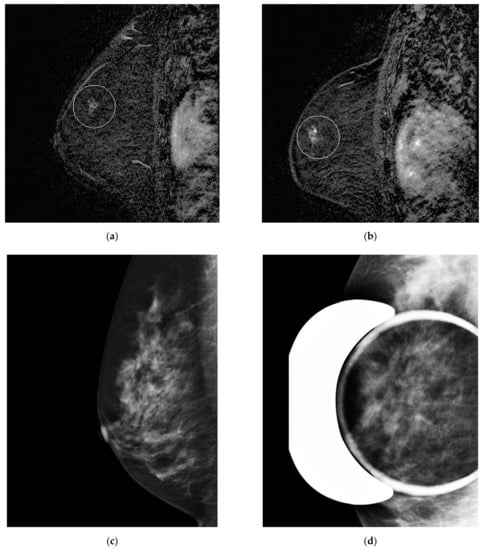

Our database included 22,000 breast MRIs from 7095 patients, carried out between 2005 and 2020. Of the 3000 malignancies investigated with MRI, 132 fulfilled our inclusion criteria, elaborated below. After excluding 28 patients, a total of 104 patients were reviewed. We consequently obtained 104 pathologically proved cancers for our analysis (Table 1). The reasons for excluding 28 patients were mostly because of inaccessible imaging data. In a few cases, patients initially were included via our research algorithm, but upon review turned out not to meet the criteria to be in the OBSP high-risk program: the biopsy results did not come back as malignant (for example in the case of in situ lobular carcinoma) or the cancerous lesion was only visible on mammogram as calcifications and not on MRI (Figure 3).

In total, 77 (74%) out of the 104 breast cancer cases included in our study were retrospectively visible on MR A and considered missed. In total, 51 were overlooked and 26 were misinterpreted (66% versus 34% of missed lesions, respectively). A total of 27 cases were non-missed cancers, i.e., classified as interval cancers (Figure 3, Figure 4 and Figure 5).

MRI characteristics did not significantly differ between overlooked and misinterpreted lesions. In our retrospective review, qualitatively, of the six cancerous lesions at the site of previous biopsy or surgery missed, four (67%) were misinterpreted as a probably benign lesion for which a follow-up was recommended and one was overlooked. (Figure 4 and Figure 5). Other causes for misinterpretation included complex cases with multiple breast lesions (2 cases), longstanding stability in size (8 cases) and benign features such as smooth margins and hyper T2 signal (10 cases). Causes for overlooked lesions included increased background parenchymal enhancement (24 cases), faint enhancement (6 cases) and a small size of less than 5 mm (21 cases) (Table 5).

In the missed cancers category, in two cases, suspicious microcalcifications seen mammographically contributed to recognizing the non-mass enhancement as abnormal on MRI.

Figure 3. Misinterpreted stable non-mass enhancement between (a) MR A and (b) MR B. Calcifications were visualized in the same location and increasing in number on (c) the concomitant mammogram and (d) magnification views.